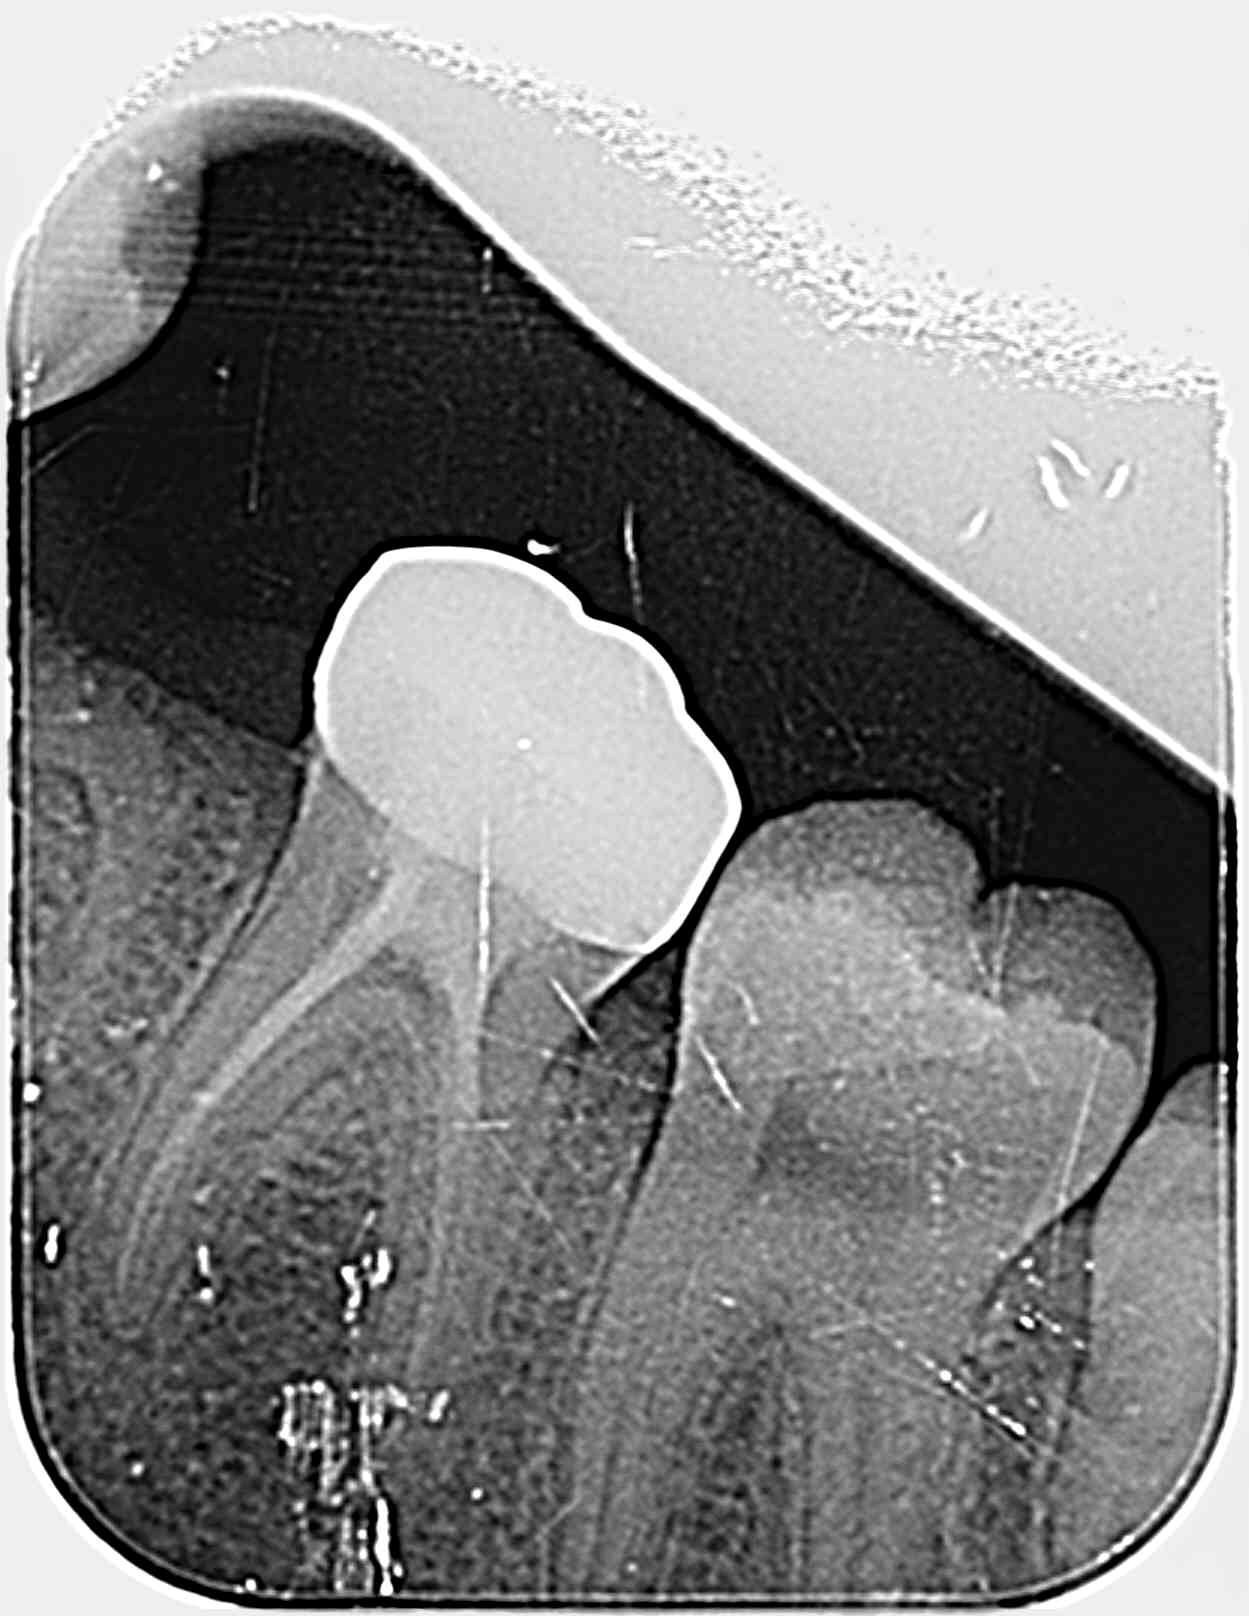

Bonjour, comment aborder traiter cette résorption interne, (l'implant à oublier pour raison financière à ce jour), bouchon MTA , verre ionomère ?

Bon burnax, je suppose que tu parles de la 36 ??

Je dirais pas résorption interne mais plutôt reprise de carie ...

Faut démonter, cureter et après tu vois combien il te reste d'épaisseur en inter radiculaire ..

Sur ta rétro griffée , ça semble moins profond que sur la pano !!

36 oui.

Résorption interne ou externe ?

Pour une carie, je trouve être fort sous-gingival .. ?

Une bio, que j'ai faite il y a 11 ans.

Concrètement, nous pouvons observer une vague radio clarté au niveau de la chambre pulpaire de 36, manifestement pas dans le même plan puisqu'elle est décalée en fonction de l'axe de la radio. Et... c'est tout.

Si il s'agit d'une reprise de carie, on a une entrée externe objectivable. Une résorption externe, c'est très rare, ça ne sonde pas et c'est asymptomatique, c'est plutôt lié à une ankylose. Une interne, il faut un parenchyme pulpaire. Donc quoi, il faut un cone beam pour diagnostiquer une carie? Je veux pas faire le parano de l'ASN, mais heureusement que les toubibs ne prescrivent pas un scanner à chaque rhume, sinon les patients vont finir fluos.

moi je vois seulement un défaut d'obturation de la chambre pulpaire

ca serait interessant de comparer à la radio post op

L'endo est belle par ailleurs, surtout sur une petite.